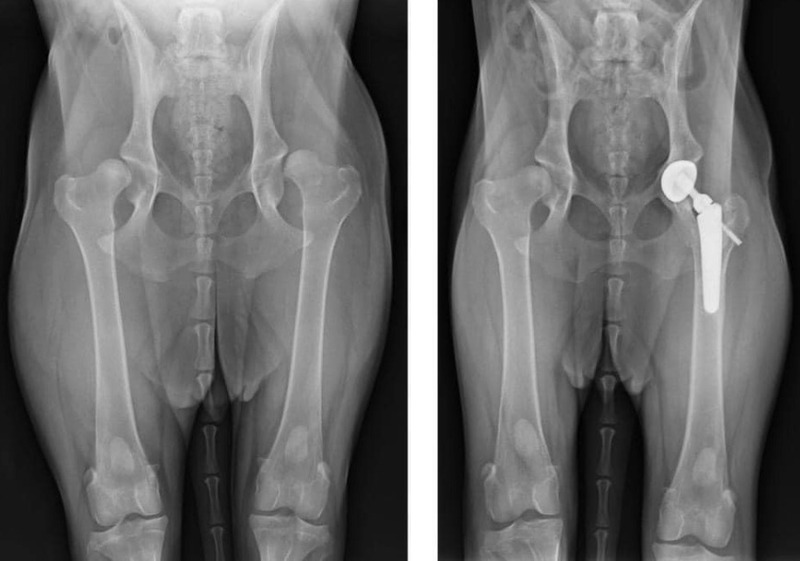

- Thoái hóa hoặc viêm khớp nghiêm trọng: Khi khớp bị tổn thương không thể phục hồi bằng thuốc, bác sĩ có thể chỉ định phẫu thuật thay khớp hoặc làm sạch khớp.

- Thoái hóa khớp và viêm khớp mãn tính: Thường xảy ra ở mèo lớn tuổi, gây đau, sưng khớp và hạn chế vận động, đôi khi cần phẫu thuật thay khớp.

- Dị tật bẩm sinh hoặc phát triển xương bất thường: Một số mèo sinh ra đã có cấu trúc khớp hông, gối hoặc khuỷu tay không bình thường, cần phẫu thuật chỉnh hình để cải thiện dáng đi.